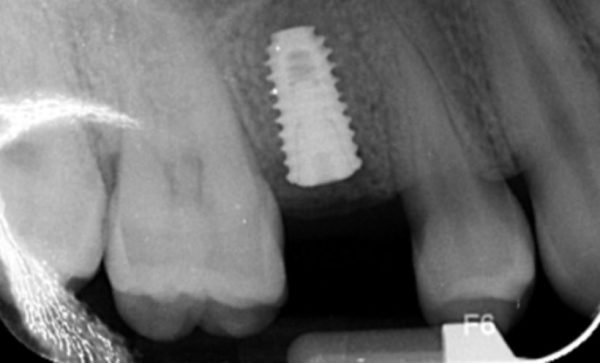

Case 29